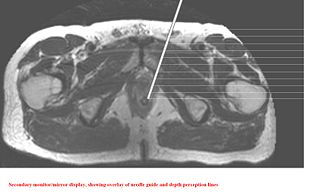

Image Overlay in clinical setup

Once the system is calibrated, and registered with patient, the software moves to next step. In this step, the entry and target points are given by mouse-clicks. The software calculates the insertion angle w.r.t vertical and insertion depth. Also, the software overlays the needle guide on the secondary monitor/mirror to assist the physician/user to perform the intervention. There is an option to reset the plan, in case the physician wishes to perform another needle intervention with same image.

After planning, in the insertion step, further depth perception lines appear in gradations of 10mms to help the physician to insert the needle at correct depth.